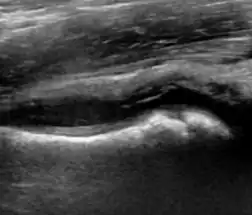

Ultrasound

Ultrasound is the first-choice technique for diagnosis of newborns hip dysplasia. In experienced hands with appropriate technology, ultrasound can also be useful during the first year of life. Some European healthcare systems encourage universal ultrasound screening in neonates between the sixth and eighth weeks. Although it shows higher initial costs caused, it leads to significant reduction in the total number and overall costs of dysplastic hips undergoing operative and nonoperative treatment.[1]

Ultrasound allows categorizing pediatric hips, according to Graf’s criteria, in four main types: normal, immature, and dysplastic (subluxed and dislocated). This classification is based on measurements of the acetabular inclination angle (alpha), cartilage roof angle (beta), and infant age. The femoral head coverage can also be determined by dividing the length of the femoral head covered by the acetabular fossa and the diameter of the femoral head. Its lower normal limits are 47% for boys and 44% for girls (Figure 11).[1]

During childhood, ultrasound is a quick method to assess hip pain and quite often may be used to avoid use of irradiating techniques, such as radiography or CT. Ultrasound allows evaluation of joint effusion, synovial thickening and neovascularity, the bone/cartilage contour, and the femoral head-neck alignment. Although sonography is extremely sensitive in detecting increased synovial fluid, it is nonspecific and cannot be used with accuracy to determine the type of fluid. Transient synovitis of the hip, despite being the most frequent cause of pain in children between 3 and 10 years, remains a diagnosis of exclusion. It usually shows anechoic fluid, but echogenic fluid can also be found. The effusion is considered pathologic when it is measured at >2 mm in thickness. The differential diagnosis is wide, including osteomyelitis, septic arthritis, primary or metastatic lesions, LCPD, and SCFE. Discrimination from septic arthritis is challenging, often requiring joint aspiration. In septic arthritis, US is able to demonstrate a hip joint effusion, synovial thickening, and cartilage damage, although the appearances are nonspecific.[1]

A step between the head and the physis can be detected in children with SCFE, while abnormalities in the femoral head contour may suggest the presence of LCPD. In both cases, radiographs are mandatory to confirm diagnosis and severity (Figure 12).[1]

Figure 12:

Normal ultrasound appearance of the femoral head-neck junction.

Joint effusion in transient synovitis of the hip.

Flattening of the femoral head in a patient with Perthes disease.

Step in the femoral head-neck junction in a patient with SCFE.

In adults, the most common application for US is to detect tendon or muscle injuries, effusion or synovitis within the hip joint or its adjacent bursae. Joint effusions may be due to many intra-articular processes and this may need another imaging technique to achieve a specific diagnosis.[1]